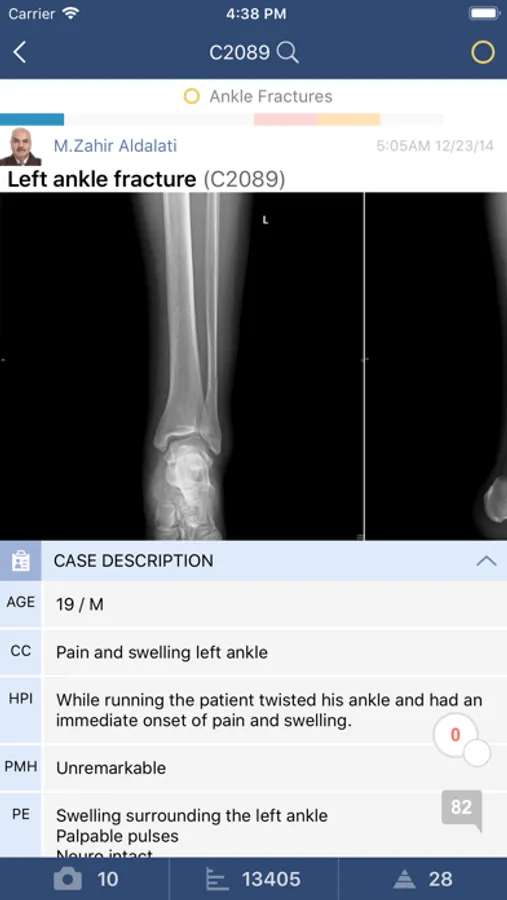

The companion APP for Orthobullets.com and Medbullets.com.

Bullets* contains medbullets and orthobullets Topics, Questions, Techniques, Cases, Videos, and Evidence. Our Testmaster allows you to create, take, and review customized exams. Article links allows for quick review of scientific abstracts and often the PDF is provided and can be viewed on your phone. Our "Home" screen allows you to monitor a thread of educational activity within our community, and it can be filtered to only include your specialty of interest. All educational activity, including the Qbank, is synced with the main platform for seamless use on both your iPhone APP and computer.